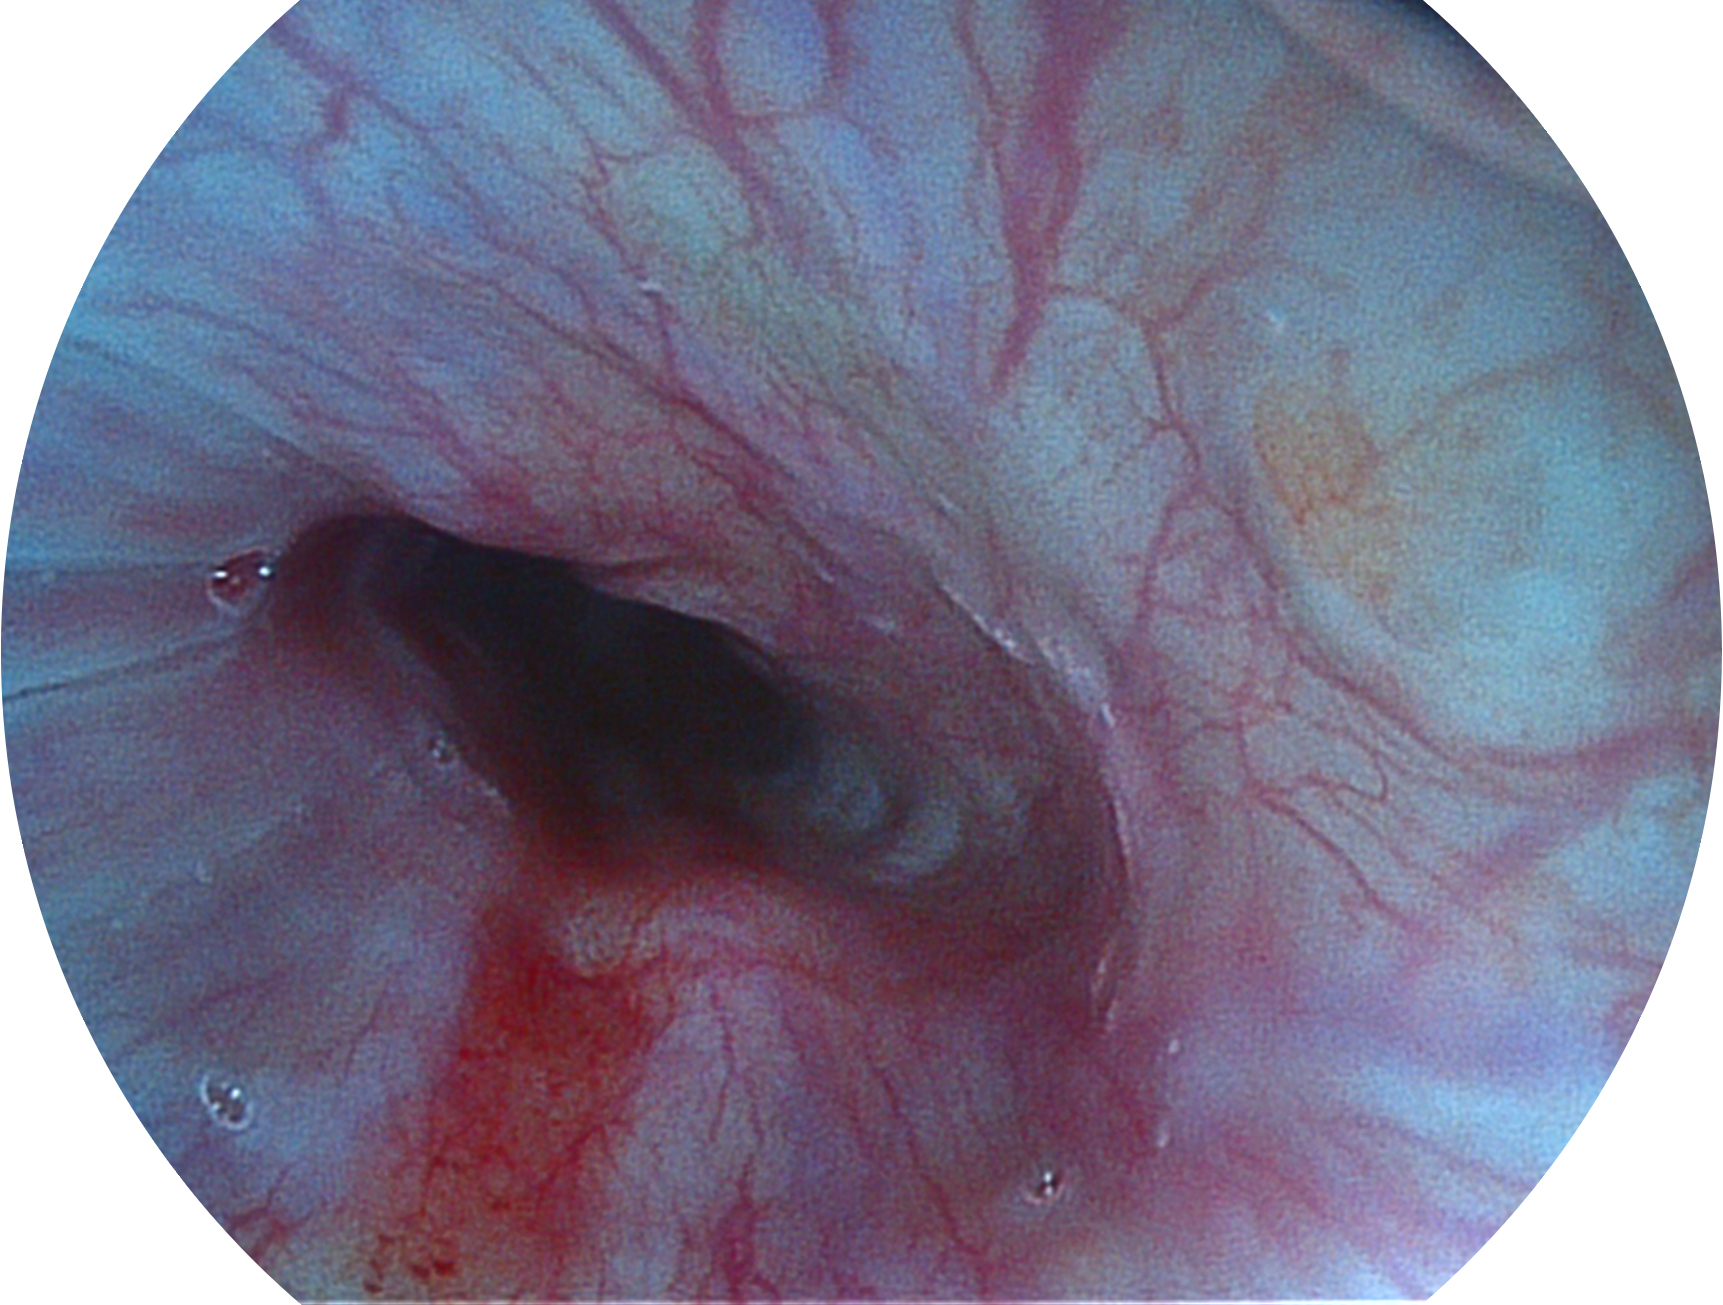

哈哈体育官网新开发的内镜染色技术,主要是基于多波长LED 光源的开发,VLS-55Q 四波长LED 光源是由四个不同颜色的LED光按照相应照明模式所规定的特定发光比例进行合束后形成,合束后形成的照明光的光谱由红光、绿光、蓝光及蓝紫光这四个不同的波段范围构成。具有更高光谱自由度,通过光谱比例的控制,实现了聚谱成像技术,英文全称为“Spectral Focused Imaging, SFI”,缩写为“SFI”和光电复合染色成像技术,英文全称为“Versatile Intelligent Staining Technology, VIST”,缩写为“VIST”。